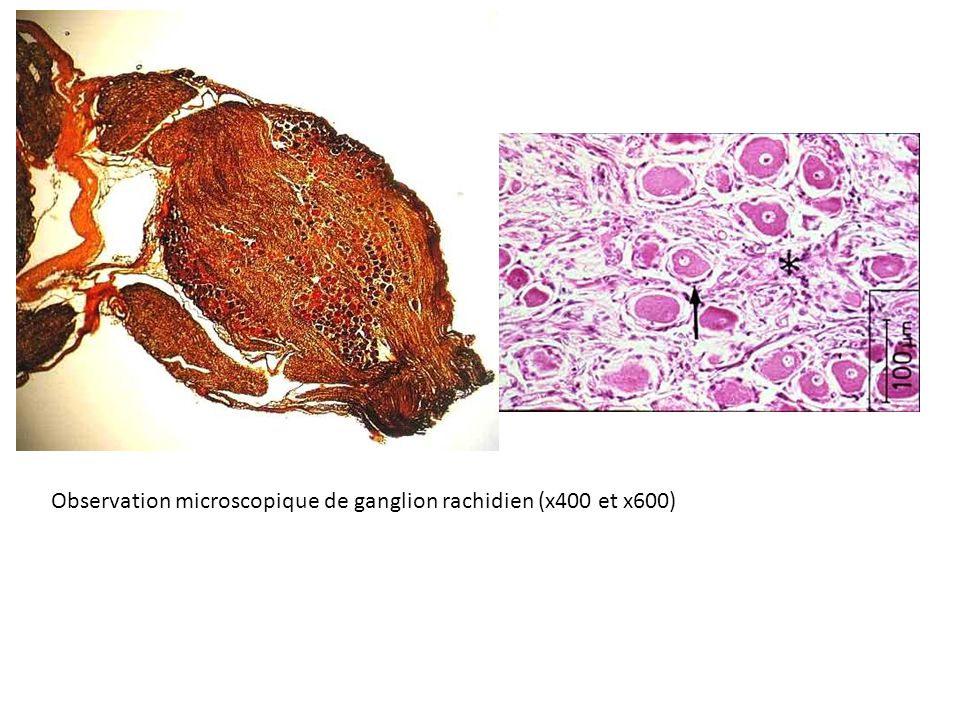

TP n°2 Le système nerveux central et périphérique / Observer - organiser

Nerf rachidien

Photo prise en TP Eléa, Théo D., Eva J., Dorian